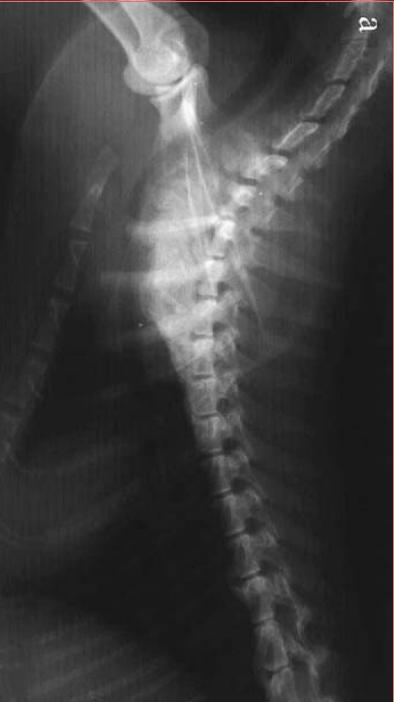

九岁 去势 公猫,长期以猪肝为主喂食自制食物。就诊时左前肢跛行,后出现霍纳氏综合征,两个月发展成瘫痪。

经病史检查,血液和影像学分析和以及血清维生素A浓度的测定,诊断为维生素A过量继发 臂 神经丛压迫。

尾颈椎和颅胸椎腹侧新骨形成